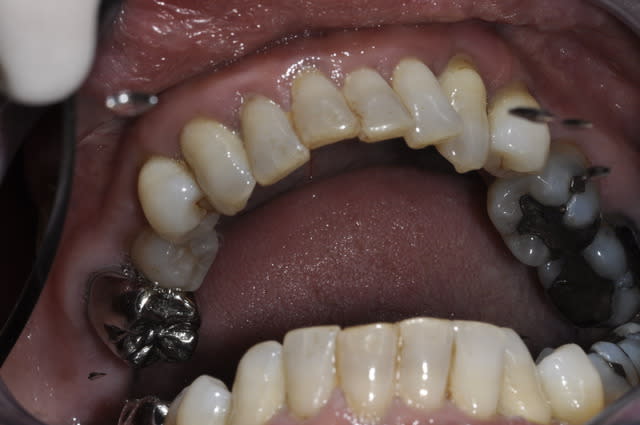

Patiente qui se presente au cabinet car ne supporte plus ses dents.

Par contre pour la mandibule je sèche un peu.

Est ce que je garde des dents ou pas?

Je pensais peut être garder de 46 à 33 avec assainissement paro et pose de 2 implants en 34/36 avec bridge sur implant.

Ou alors j'extrais tout et je fais une prothése implanto portée?